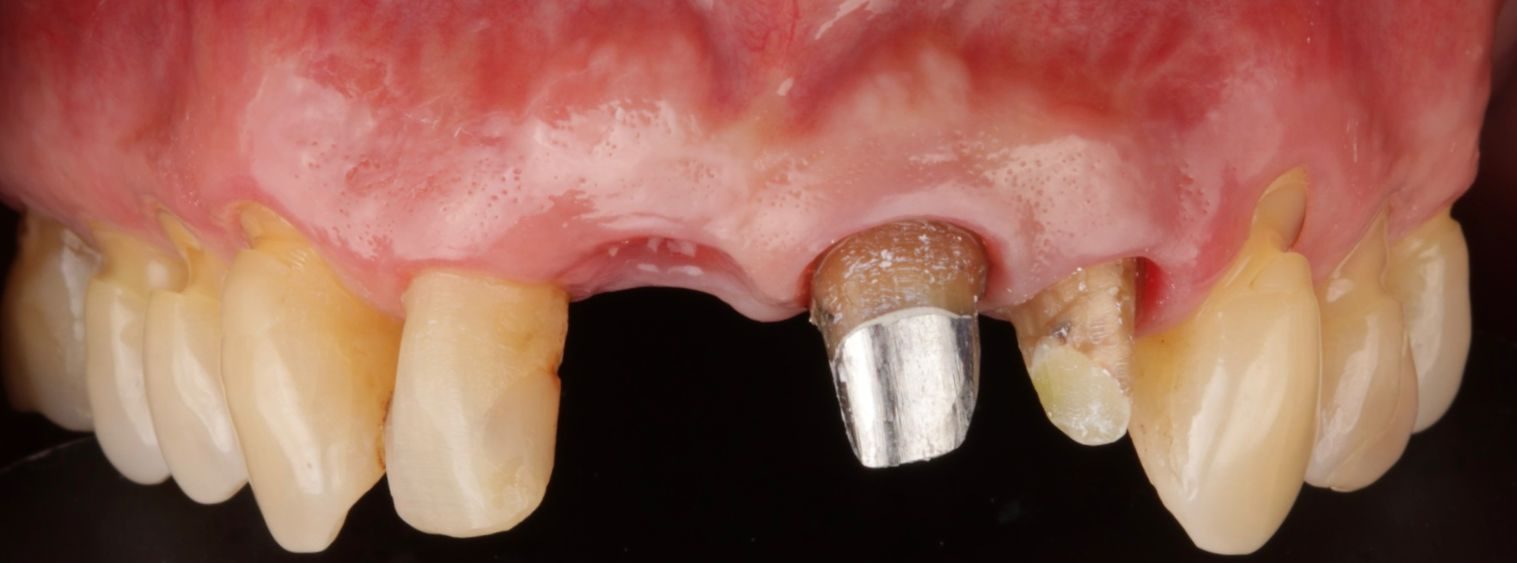

Mediante anestesia local, se colocará minuciosamente el implante dental en el hueso y se cerrará la herida con un par de puntos de sutura si se requiere. Depende del caso y la planeación se pueden realizar procedimientos de carga inmediata donde el implante puede ser restaurado con un diente provisional durante el tiempo de osteointegración. Este procedimiento se puede llevar a cabo con sedación consciente si el paciente lo prefiere.

Después de la cirugía para la colocación de los implantes dentales, se recomienda la ingesta adecuada de medicación para un postoperatorio cómodo y lo menos doloroso posible. También se entregan recomendaciones postoperatorias que incluyen la aplicación de hielo y otros cuidados básicos. Adicionalmente se revisa la cicatrización de la encía y se retiran puntos de sutura. Aunque la encía se recupera en una semana, el período de integración del implante con el hueso dura de 3 a 6 meses (cada caso clínico es individual), y durante este proceso se definirá algún tipo de prótesis provisional.

Fase rehabilitadora